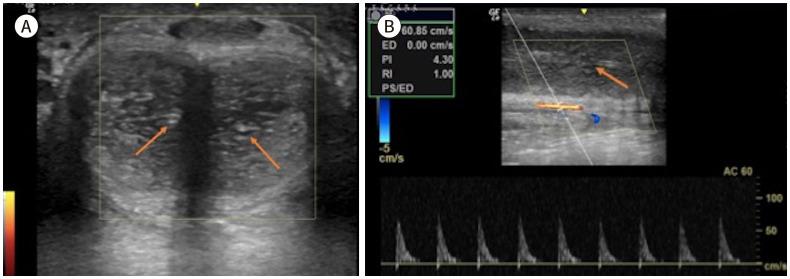

Penile emergencies are uncommon and can be categorized as having infectious, vascular, traumatic, or multifactorial etiologies. To facilitate early diagnosis and treatment during emergency, US and color Doppler imaging are imperative. US depicts hypoechoic collections regardless of the presence of air foci in infections like abscess and Fournier's gangrene. Color Doppler imaging is conducted to evaluate vascular conditions such as penile Mondor disease (PMD) and priapism. PMD is indicated by the absence of color flow and non-compressibility of dorsal penile vein. Priapism can be categorized based on cavernosal artery flow: high flow and low flow. In traumatic injuries like penile fracture, US reveals breach in tunica albuginea with hematoma. Peyronie's disease can be multifactorial in origin and the imaging is commonly visualized as thickening of the tunica albuginea and echogenic calcified plaques. Urethral injuries are urethral discontinuity with adjacent collection. Urethral calculus is visualized as echogenic focus with posterior acoustic shadowing. Therefore, effective collaboration between radiologists and urologists is required for appropriate initial diagnosis and prompt treatment.

阴茎急症并不常见,可分为感染性、血管性、创伤性或多因素病因。为便于在急诊时进行早期诊断和治疗,超声(US)和彩色多普勒成像必不可少。在诸如脓肿和福尼尔坏疽等感染中,无论是否存在气灶,超声均能显示低回声液性聚集。进行彩色多普勒成像以评估血管状况,如阴茎蒙多氏病(PMD)和阴茎异常勃起。阴茎蒙多氏病表现为阴茎背静脉无血流信号且不可压缩。阴茎异常勃起可根据海绵体动脉血流分为:高流量型和低流量型。在阴茎骨折等创伤性损伤中,超声显示白膜破裂并伴有血肿。佩罗尼氏病的病因可能是多因素的,影像学表现通常为白膜增厚和回声增强的钙化斑块。尿道损伤表现为尿道连续性中断并伴有相邻液性聚集。尿道结石表现为伴有后方声影的回声增强灶。因此,放射科医生和泌尿外科医生之间需要有效协作,以进行恰当的初步诊断和及时治疗。